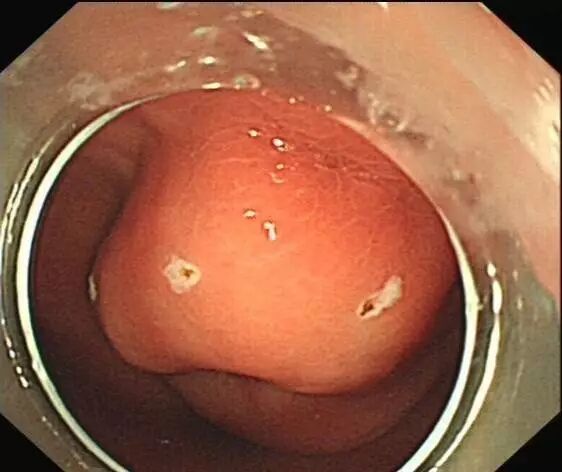

OTSC在消化道出血治疗中的应用

内镜夹怎么不掉CJP每周一帖--OTSC吻合夹系统在经内镜治疗消化道出血、穿孔及瘘中的应用_https://www.jmylbn.com_新闻资讯_第11张